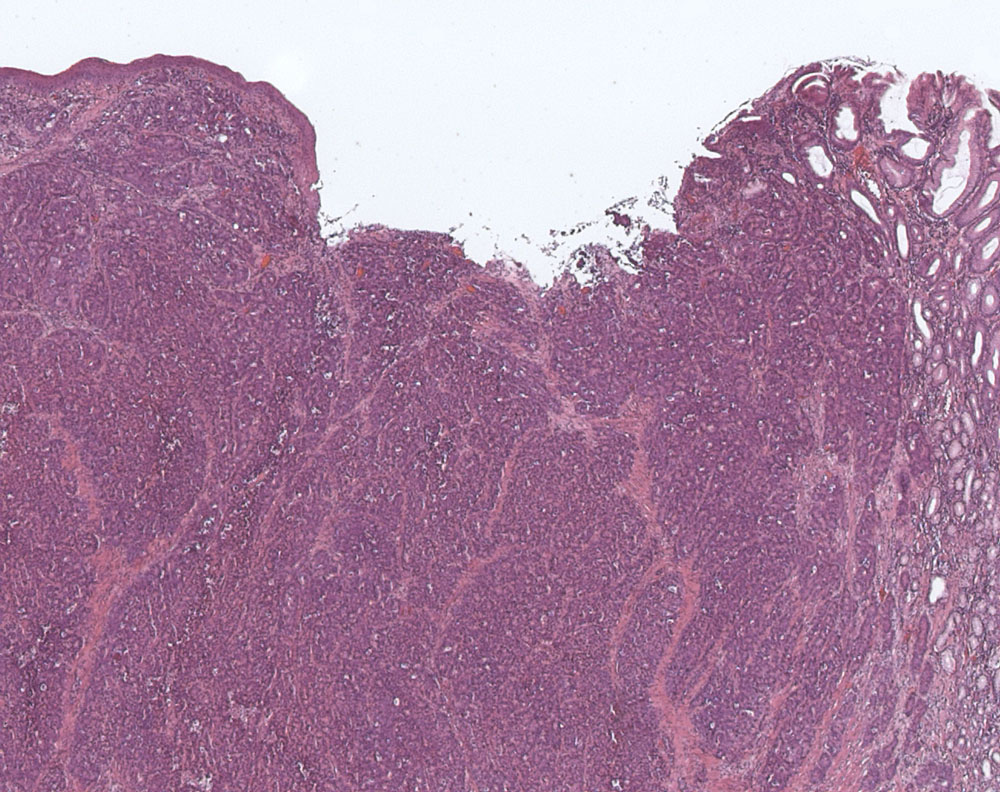

Grosszelliges neuroendokrines Karzinom des Ösophagus

Oesophagogastrischer Uebergang

Ulzerierter Tumor am gastroösophagealen Übergang. Das Karzinom bildet basophile Tumorzellformationen mit dos à dos liegenden Drüsen.

Diffuse Positivität für Synaptophysin. Ki-67 Proliferationsrate 60%. TTF-1 negativ.

80 jährige Patientin. Karzinom des gastroösophagealen Übergangs.

Histologie

25